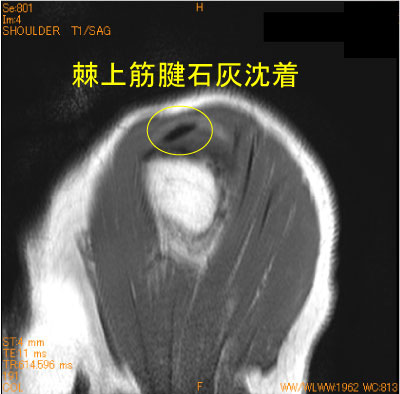

石灰沈着腱板炎-肩関節MRI-

60代男性。ゴルフ時の疼痛肩。

MRI撮影時に必ずしも石灰沈着が指摘されている訳ではない。

常日頃、筋内腱のlow signalの走行、大きさを脳裏に焼き付けておいて、異常なlow signalの存在に気がつく必要がある。

![]() Obl. Sag T1WI |